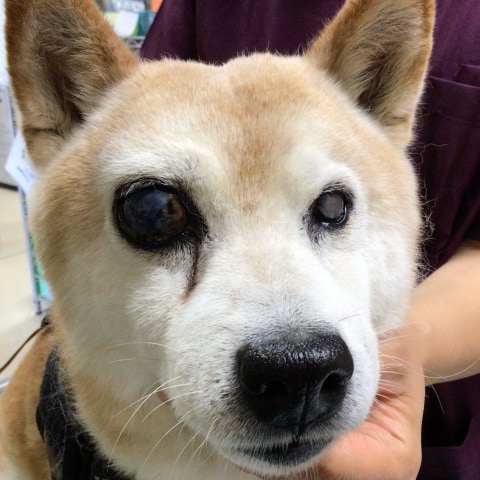

目が赤く、腫れている

眼房内の出血があり眼圧測定にて高眼圧を確認しました。緊急的な点眼薬による眼圧降下治療を実施後、網膜剥離あり視覚回復せず、疼痛が継続していたため疼痛管理を目的とし強膜内シリコンインプラントを実施しました。

眼圧の上昇は目が腫れることで痛みや出血、視神経障害による失明を引き起こすことがあり早期発見、早期治療が大切です。目が腫れている、反対の目に比べて前に出てきている、目が赤い、目を痛がるなどの症状があればお早めにご相談くださいね。